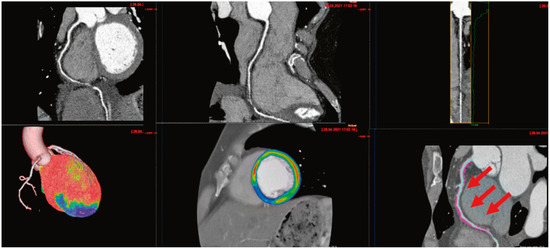

Myocardial infarction with nonobstructive coronary arteries (MINOCA): Myocardial infarction (MI) with non-obstructive coronary arteries (MINOCA) is defined as MI according to the fourth universal definition of MI [1] without coronary stenosis ≥50% on...